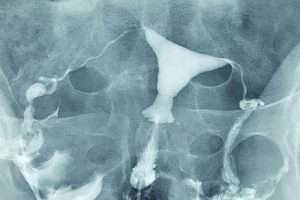

Tüplerde Sıvı Birikmesi

İki Taraflı Salpenjitis Istmica Nodosa (SIN) ve Hidrosalpinks